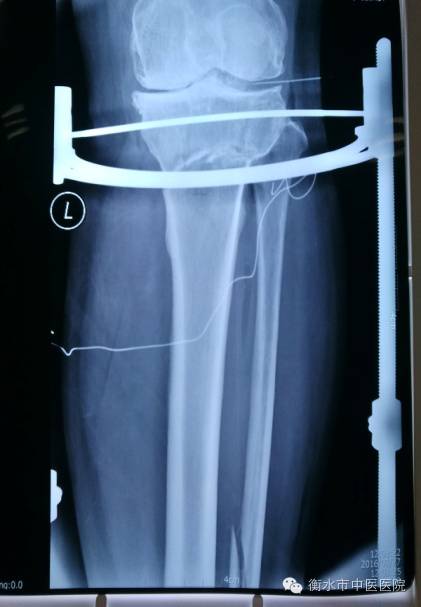

【病例】骨伤科在与北京望京医院骨伤科成为协作科室后,积极吸取先进经验和技术,与2016年1月27日邀请望京医院骨伤科金阳主任医师亲自为在我院治疗的一名经受膝关节内翻畸形多年病痛折磨的45岁女性住院患者进行了胫骨上段高位截骨+孟氏固定架外固定术,不仅为患者矫正了膝内翻,解除了病痛,而且大大降低了治疗费用,现患者已可以正常下床活动。

(术后)